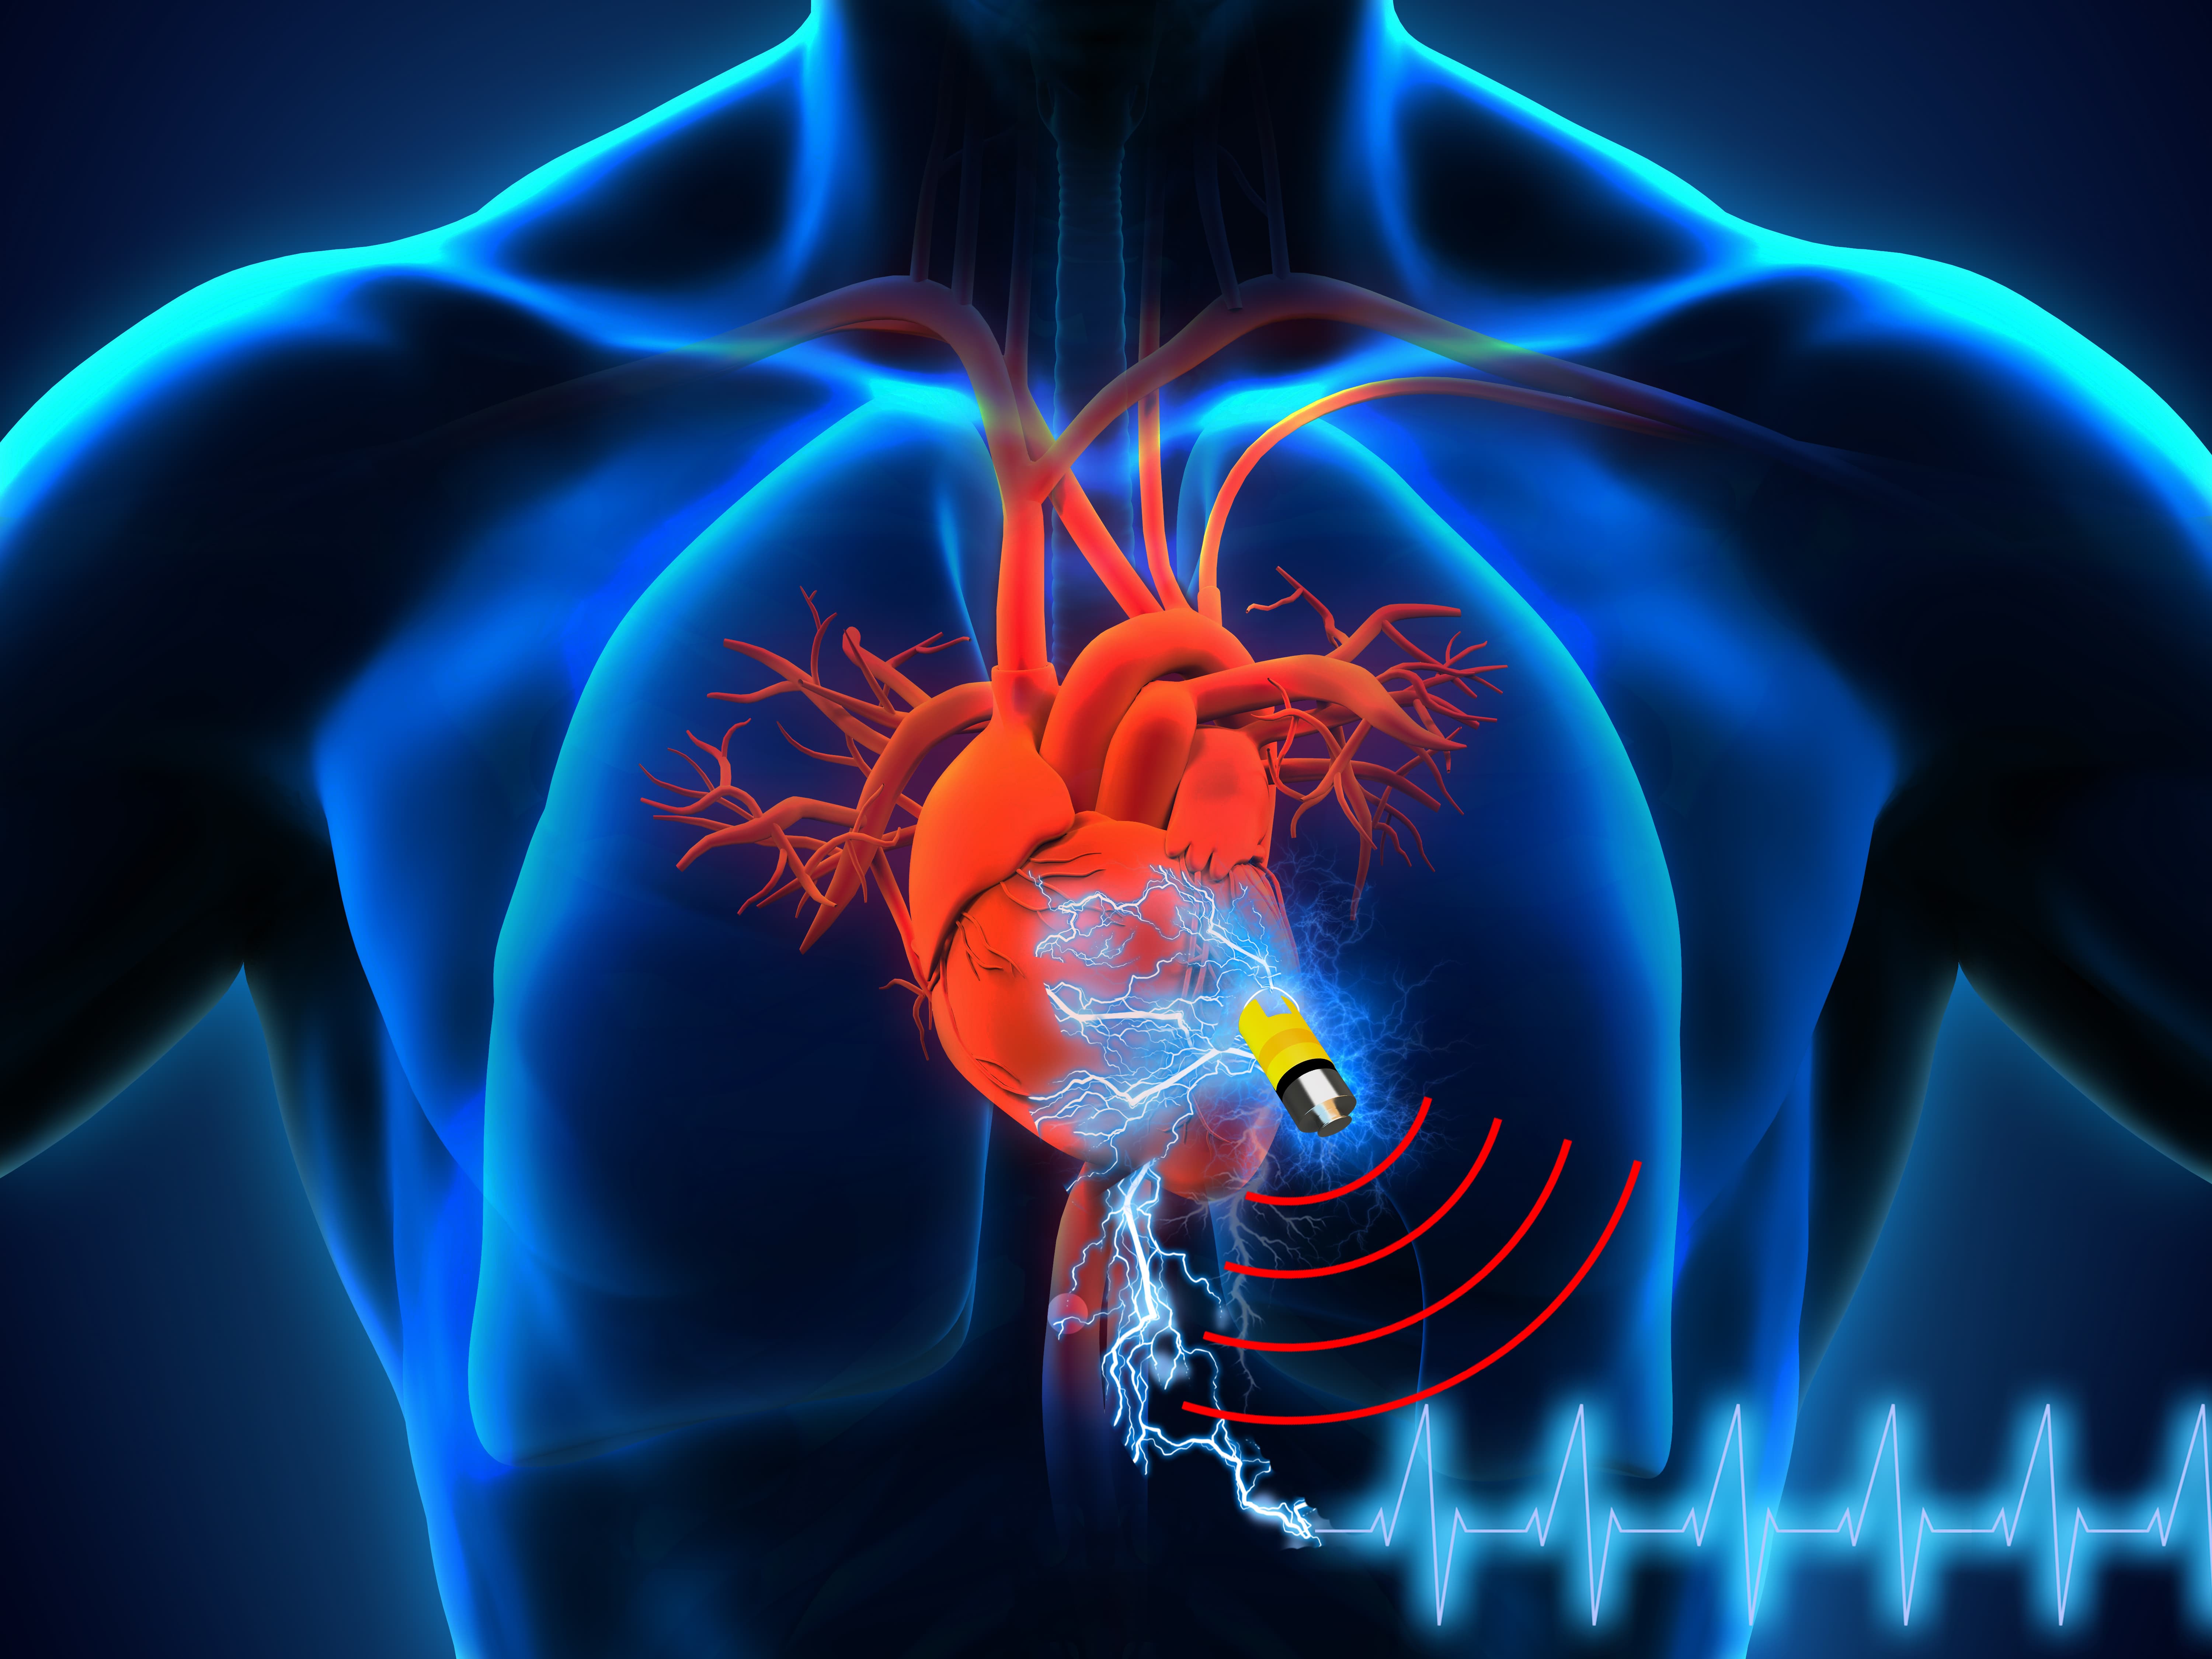

Изображения и визуализация внутренних органов человека

Раздел: Секреты мастерства